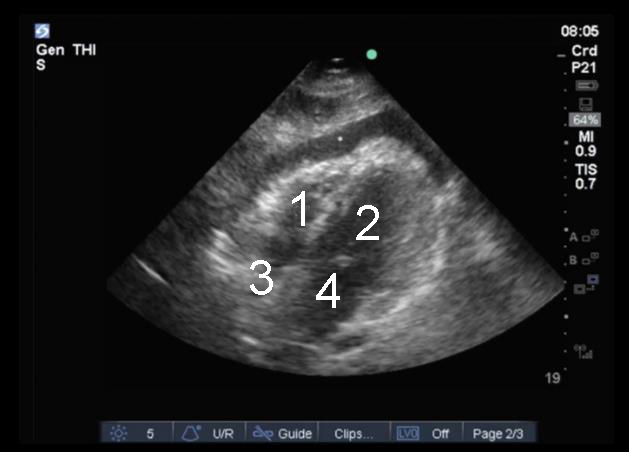

心脏剑突下中度积液图像

右心室 (RV)

左心室 (LV)

右心房 (RA)

左心房 (LA)